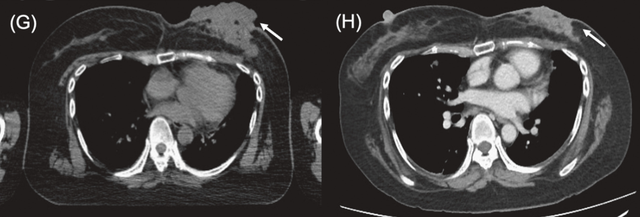

病例4

一名43岁女性,患左侧三阴性乳腺癌,因骨转移导致脊髓压迫,并接受了姑息性椎板切除术。由于左侧乳房出现伴有皮肤侵犯的疼痛性复发灶,患者于2025年7月23日接受了BNCT治疗,2025年8月21日的随访CT显示左胸壁病灶缩小。